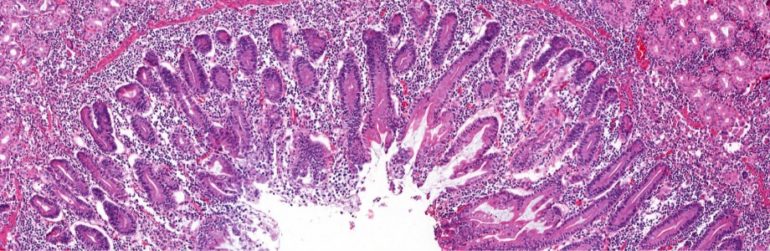

Contrairement aux cellules du tissu adipeux blanc, les cellules beiges sont riches en mitochondries, et sont donc capables de produire de la chaleur à partir du gras. La transformation du tissu adipeux blanc en beige, phénomène appelé «browning», est donc un moyen de brûler du gras.

Le Prof Patrice Cani et d’autres chercheurs de l’Université Catholique de Louvain ont découvert que l’enzyme NAPE-PLD du tissu adipeux apparaît comme un acteur majeur dans le contrôle du mécanisme énergétique, parce qu’elle favorise précisément la production de tissu adipeux beige.

Ces effets sont la conséquence de la disparition presque complète des cellules beiges.